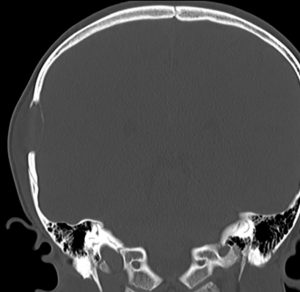

CTで典型的な頭蓋骨の打ち抜き像 punched out lesion が左頭頂骨にあります。これだけでLCHと診断がつくような画像です。

頭蓋骨のLCH

- 上の写真は,子供の右の頭頂骨にできたLCHで,頭部病変では最も多く見られるタイプです

- 頭蓋骨が丸く抜けるように破壊されるのでpunched out lesionと表現されます